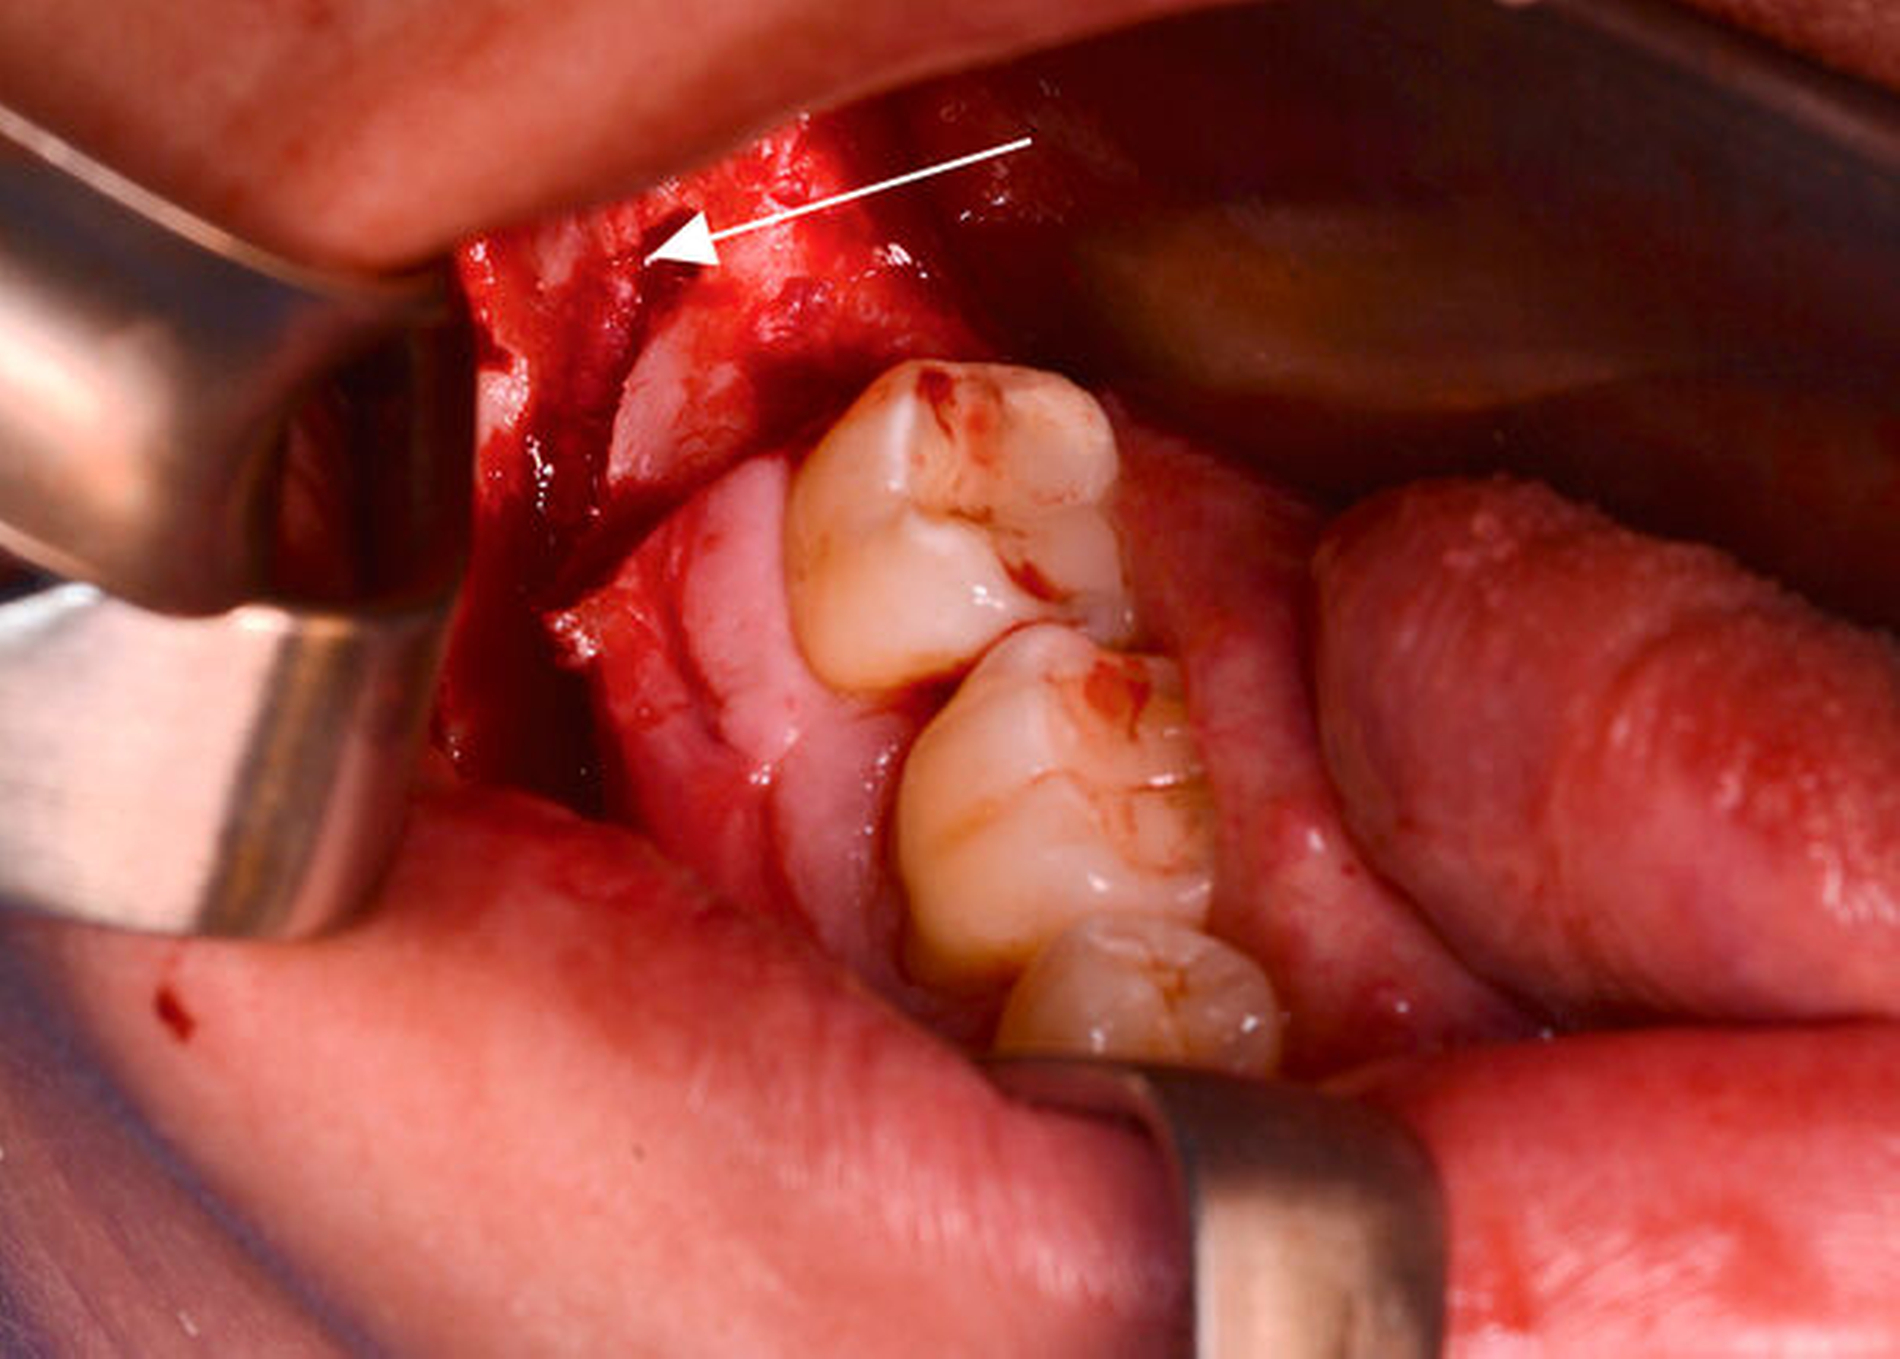

Nach krestaler Schnittführung erfolgte die Darstellung des vestibulären Unterkiefers. Beginnend am Foramen mentale wurde mittels Piezochirurgie eine schonende Osteotomie des Knochens entlang des Nervverlaufs durchgeführt. Nach Darstellung des retromolaren Anteils des Nervkanals zeigten sich eine deutliche Kontinuitätsunterbrechung des Nervus alveolaris inferior ebenso wie eine neurinomverdächtige Struktur, die im Rahmen der Operation entfernt werden konnte (Abbildung 3). Nach Entnahme des Nervus-suralis-Interponats aus der rechten Knöchelregion (Abbildung 4) wurde der residuale Nervus alveolaris inferior angefrischt und das Interponat mittels intrafaszialer Nähte (Größe 10-0) mit den beiden Enden des Nervus alveolaris inferior anastomisiert (Abbildung 5). Anschließend wurde der Nerv mit einer Platelet-rich-fibrin (PRF-)Membran abgedeckt und der entstandene Defekt mit dem entnommenen Knochendeckel verschlossen (Abbildung 6).